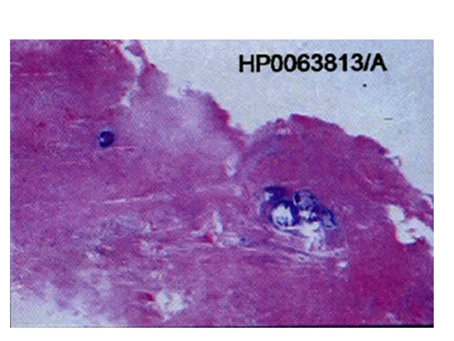

The investigations advised included the complete blood picture, intraoral periapical radiograph, maxillary occlusal view, panoramic radiograph and CBCT. Periapical radiograph and maxillary left lateral topographical occlusal view a revealed diffuse patchy radiolucency in region of 26, 27 along with multiple flecks of fine calcifications and hypercementosis was seen with respect to 28 (Figure 2) (Figure 3). Panoramic view revealed radiopacity extending from 24 to tuberosity and encroaching onto the maxillary sinus (Figure 4). To make out the exact extent of the lesion CBCT imaging was planned. CBCT sections showed mixed radiopaque radiolucent (predominately radiopaque) lesion, with well defined borders, extending from 24 till tuberosity region (Figure 5) measuring anteroposteriorly 4cm ,superoinferiorly 5cm ,and mesiodistally around 2.5cm in dimension. The pterygoid plates though intact, the lesion however did superimpose on the maxillary sinus. No secondary reaction in the sinus could be appreciated. With a clearer picture on the extent of the lesion, we took the next step towards the management.

Figure 2 The complete blood picture, intraoral periapical radiograph, maxillary occlusal view.

Figure 3 Periapical radiograph and maxillary left lateral topographical occlusal view.